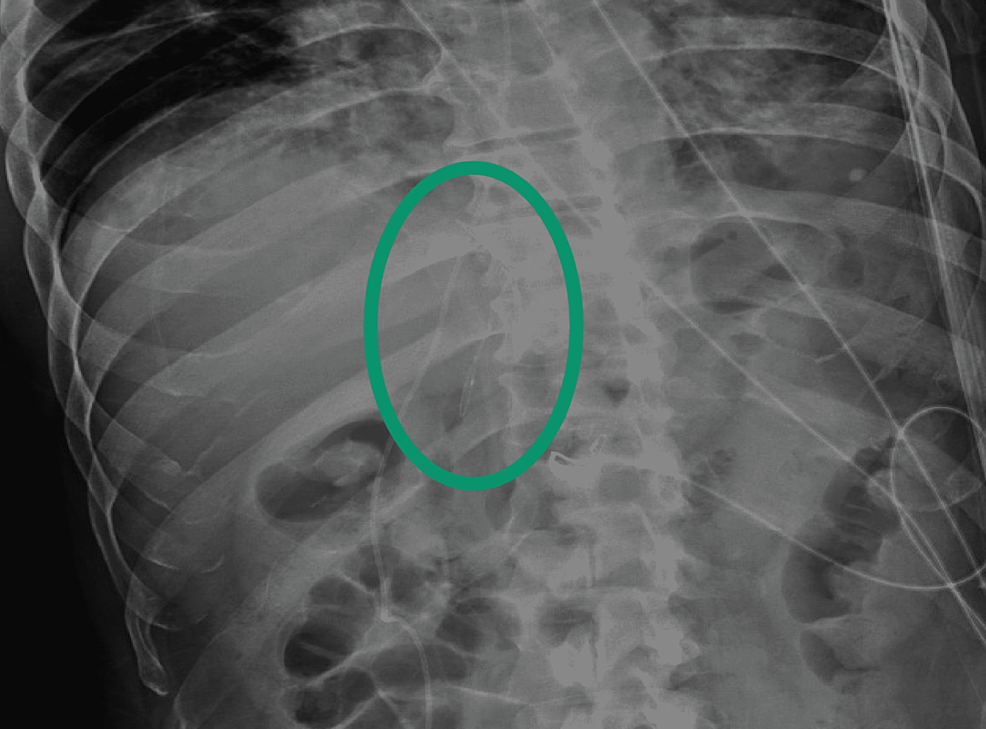

CT image of abdomen showing malpositioned IVC filter with extracaval Ivc Filter X Ray Image identification of permanent and retrievable ivc filters and individual filter types on diagnostic imaging is important. ivc filter strut penetration at ct. inferior vena cava filters (ivc filters) are indicated as a treatment. Ivc Filter X Ray Image.

Ivc Filter X Ray Image ivc filter strut penetration at ct. ivc filter strut penetration at ct. identification of permanent and retrievable ivc filters and individual filter types on diagnostic imaging is important. inferior vena cava filters (ivc filters) are indicated as a treatment.

inferior vena cava filters (ivc filters) are indicated as a treatment. identification of permanent and retrievable ivc filters and individual filter types on diagnostic imaging is important. ivc filter strut penetration at ct.